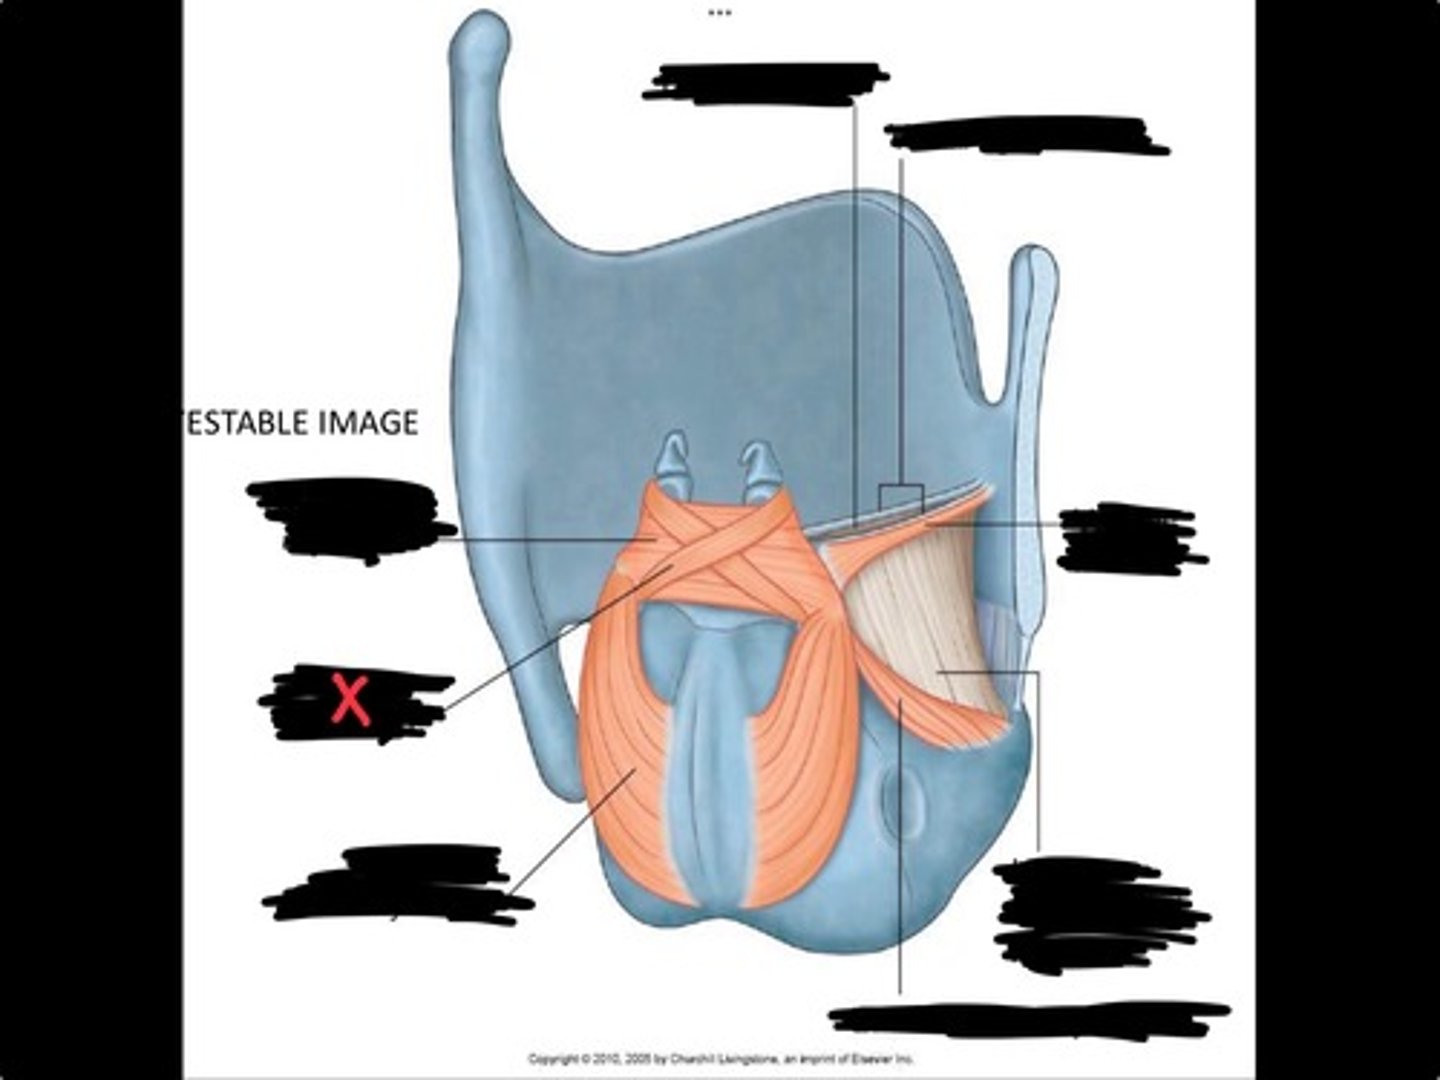

Vocal process of arytenoid

Conus elasticus

Vestibular ligament

Quadrangular membrane

Epiglottis

vocal ligament

Aryepiglottic ligament

Muscular process of arytenoid

Corniculate cartilage

Posterior crico arytenoid

oblique arytenoid

transverse artyenoid

Rima glottidis

Vocal ligament

Vocalis muscle

Lateral cricothyroid ligament

Lateral cricoartenoid